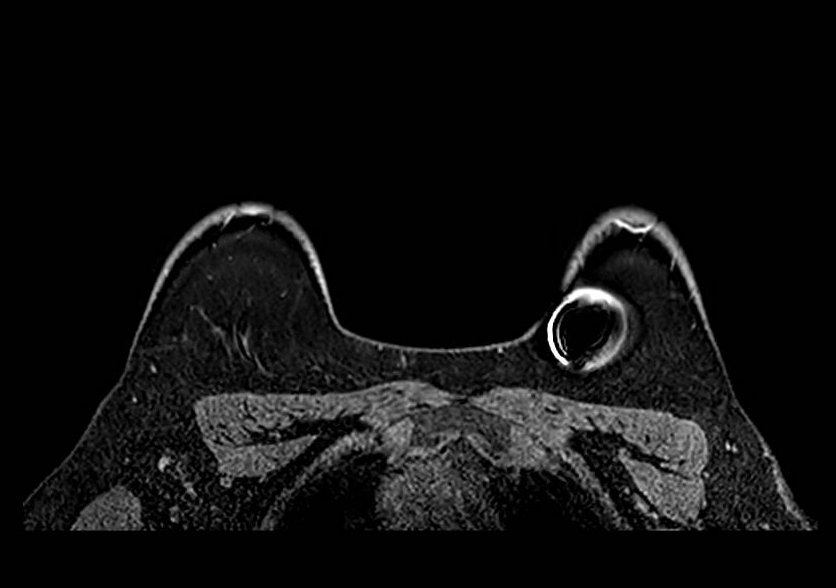

Gibbs ring artifact most noticable at implant interface (axial, IR sequence)

Gibbs ringing is a Fourier truncation artifact from finite k-space sampling. Inverse FFT of truncated data fails to represent the highest spatial frequencies at abrupt transitions, generating thin parallel bright/dark bands near high-contrast boundaries.

In breast MRI, it is easiest to see at skin-air, skin-parenchyma, and implant margins, especially in the phase-encode direction and on high-contrast sequences (e.g., T2). Reduce it by increasing phase-encode steps (more k-space lines) at scan-time cost; zero-fill interpolation can smooth the appearance but does not recover true spatial resolution. Recognition of the characteristic parallel-band pattern of Gibbs ringing helps differentiate it from true lesions.